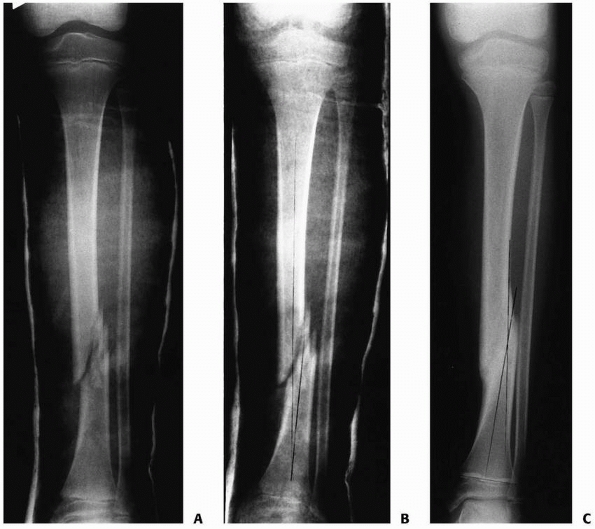

FIGURE 25-8 Developmental valgus after a proximal tibial metaphyseal fracture and subsequent corrective osteotomy. A.

Radiograph taken 6 months after a fracture of the proximal tibia. The injury was nondisplaced. The scar from the initial proximal metaphyseal fracture is still seen (arrow). This child developed a moderate valgus deformity of the tibia within 6 months of fracture. B. A proximal tibial corrective osteotomy was performed. C. Two months postoperatively, the osteotomy was healed and the deformity corrected. D. Five months later, there was a recurrent valgus deformity of 13 degrees. (Courtesy of John J.J. Gugenheim, MD.) |